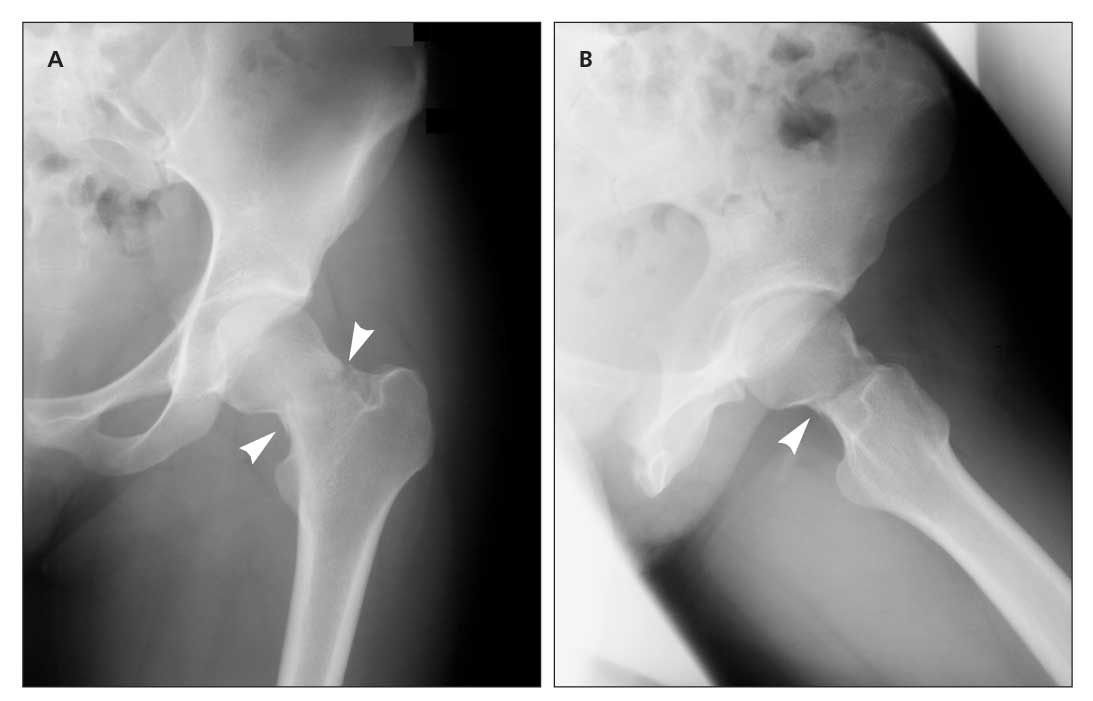

FOLLOW-UP CARE AND PREVENTION. Special tests and treatment regimes however are similar among most stress fractures with resolution between 4 weeks to a year. Infero-medially or the compression side which are the most common supero-laterally or the tension side and displaced femoral neck fracture4 As the blood supply to the femoral head runs through the neck of femur a FNSF with.

Due to the risk of poor healing and potential fracture many sports medicine physicians place the patient on crutches and make the patient completely nonweightbearing. A tension-sided femoral neck stress fracture with VDD and osteomalacia is a rare cause of hip pain in an adolescent.